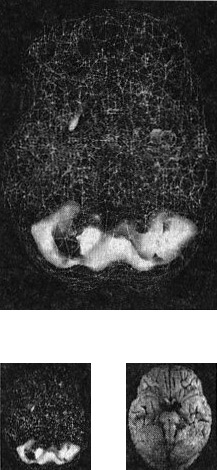

Когда мозг работает правильно, у вас все хорошо Когда мозг не в порядке, в жизни начинаются неприятности Именно мозг определяет эффективность вашей жизни. Этот принцип выглядит простым, но на самом деле он достаточно неоднозначный и может вызвать тревожность. Основная идея заключается в том, что мозг должен функционировать оптимально. Когда он работает правильно, вам легче оставаться эффективным родителем, ребенком, партнером, другом, коллегой, менеджером или общественным деятелем. Когда мозг функционирует правильно, вы имеете полный доступ к своему истинному Я. С другой стороны, если мозг болен, начинаются трудности в работе, отношениях, наедине с собой и в компаниях. Становится труднее проявлять свои лучшие качества и сильные стороны, нередко люди действуют вопреки своим ценностям, целям и представлениям о нравственности. Принцип 2 Когда мозг работает правильно, у вас все хорошо. Когда мозг не в порядке, в жизни начинаются неприятности Я вывел этот принцип в результате интерпретации сотен томограмм моих пациентов, поскольку не только читаю сканы, но и напрямую работаю с людьми и их семьями, изучаю историю их жизней. Уже в самом начале моей работы с томографией стало очевидно, что существует зависимость между качеством функций мозга на сканограммах и умением моих пациентов принимать решения, ставить цели и поддерживать отношения. Анализируя снимки, я стал размышлять о разнице между двумя типами поведения, которые я называю волевым поведением (управляемым силой воли) и мозговым поведением (управляемым неконтролируемыми импульсами мозга). Реализовывать команды силы воли возможно только при здоровом мозге, поскольку лишь он позволяет людям делать осознанный выбор и в любой ситуации действовать себе во благо. Волевое поведение продуктивно, оно способствует достижению целей, которые вы сами поставили. Например, приняв решение поступить в медицинский институт, человек должен очень усердно учиться, чтобы выдержать сложные экзамены. Прежде чем объяснить, что такое «мозговое поведение», я хочу сделать небольшое отступление, чтобы рассказать о томографии, которую мы проводим в наших клиниках. Она называется ОЭКТ — однофотонная эмиссионная компьютерная томография — и относится к области ядерной медицины, то есть для оценки кровообращения и схем активности мозга используются крошечные дозы радиоизотопов. Сканограммы ОЭКТ отличаются от типичных анатомических снимков МРТ и КАТ, которые показывают строение мозга. ОЭКТ показывает только степень активности разных областей мозга — то, как он работает. Результаты сканов ОЭКТ очень легко интерпретировать. Нужно посмотреть на области мозга, которые работают хорошо, области, которые функционируют чересчур активно («перегреты») и на недостаточно активные области. Затем мы сравниваем изучаемый скан с большой базой данных здоровых и абнормальных томограмм. В этой книге используют трехмерные снимки мозга двух видов. Первый — это трехмерные снимки поверхности, которые фиксируют верхние 45 % активности мозга. На них показано кровообращение в коре мозга и подкорковых областях. По этим снимкам мы определяем области нормального кровообращения и области со сниженным доступом крови. С помощью таких томограмм выявляют инсульты, травмы и ущерб от наркотиков. Снимок здорового мозга должен показать ровную симметричную активность по всей поверхности коры мозга (рис. 2.1 и 2.2). Трехмерное изображение поверхности здорового мозга ОЭКТ (вид поверхности сверху и снизу) Рис. 2.1 Вид сверху Полная симметричная активность ![]() Рис. 2.2 Вид снизу Полная симметричная активность ![]() Сниженная активность выглядит на подобных сканах как дыра или вмятина. Эти «дыры» и «провалы» не означают, что активность мозга в этих местах совсем на нуле, она просто снижена, так как компьютер настроен показывать только верхние 45 % активности. Все, что меньше этого значения, выглядит как дыра или вмятина. Порог в 45 % выбран, поскольку он соответствует двум стандартным отклонениям от нормы [1] и, согласно нашим данным и данным других исследователей, является оптимальным для диагностических целей. Второй тип томограмм — это трехмерные функциональные снимки, в которых компьютер сначала вычисляет среднюю активность мозга, а затем показывает верхние 15 % активности. Они помогают увидеть гиперактивные области, что полезно в диагностике припадков, разных типов тревожности и депрессии. Здоровый трехмерный функциональный снимок (рис. 2.3 и 2.4) должен показывать активность (белым цветом) в задней части мозга (мозжечке) и визуальной, или затылочной, коре и среднюю активность в остальных местах (показано сеткой). Трехмерное изображение функциональной активности здорового мозга ОЭКТ (вид поверхности сверху и снизу) Рис. 2.3 Вид сверху ![]() Рис. 2.4 Вид сверху ![]() Примечание: В тексте книги будут использоваться иконки, которые помогут читателю понимать сканограммы и увидеть их отличия от нормы. Рис. А состоит из двух иконок: трехмерного изображения поверхности здорового мозга, вид сверху; и модели мозга с той же самой перспективы. ![]() Рис. Б показывает трехмерный снимок поверхности здорового мозга, вид снизу, а нижняя иконка — это модель мозга с той же перспективы. ![]() Рис. В показывает трехмерную картину активности здорового мозга, вид сверху, а ниже показан мозг в этой проекции. ![]() |